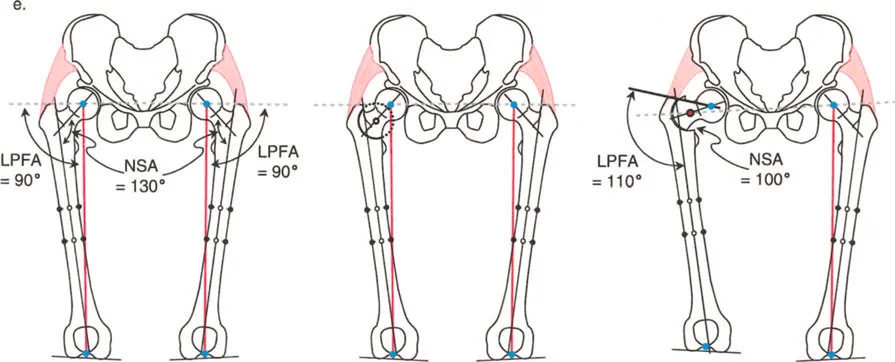

يستخدم جراحو العظام عدة زوايا لقياس محاذاة مفصل الورك وعظم الفخذ، وهي حاسمة في تشخيص التشوهات وتخطيط العلاج:

- الزاوية بين عنق وجسم الفخذ (Neck-Shaft Angle - NSA): هي الزاوية بين محور عنق الفخذ ومحور جسم الفخذ.

- الزاوية الطبيعية: تتراوح عادة بين 125° و 135°.

- كسع الورك (Coxa Vara): تحدث عندما تكون هذه الزاوية أقل من الطبيعي (أقل من 120°)، مما يجعل عنق الفخذ أكثر أفقية.

- فحج الورك (Coxa Valga): تحدث عندما تكون هذه الزاوية أكبر من الطبيعي (أكثر من 140°)، مما يجعل عنق الفخذ أكثر عمودية.

- الزاوية الميكانيكية لعظم الفخذ القريب (Mechanical Proximal Femoral Angle - MPFA): تقيس العلاقة بين محور عظم الفخذ ومستوى المدور الكبير.

- الزاوية الجانبية لعظم الفخذ القريب (Lateral Proximal Femoral Angle - LPFA): تقيس ميل الجزء العلوي من عظم الفخذ.

تؤثر هذه الزوايا بشكل مباشر على ميكانيكا مفصل الورك، وخاصة على ذراع الرافعة للعضلات المبعدة للورك. عندما تكون هذه الزوايا غير طبيعية، يزداد الضغط على المفصل، وتضعف العضلات، مما يؤدي إلى الألم والعرج وتآكل المفصل.

ب. قطع العظم الفاروسي (Varus Osteotomy)

- متى يستخدم: يُطبق في حالات فحج الورك (Coxa Valga)، حيث تكون الزاوية بين عنق وجسم الفخذ كبيرة جدًا، أو في حالات التهاب المفاصل التنكسي (الخشونة) لتحويل مناطق تحمل الوزن في المفصل، أو عندما يكون رأس الفخذ بيضاوي الشكل.

- الهدف: تقليل الزاوية بين عنق وجسم الفخذ، مما يزيد من ذراع الرافعة للعضلات المبعدة ويقلل الضغط على المفصل. قد يؤدي هذا إلى إزاحة المدور الكبير للأعلى، مما يستدعي إجراء نقل للمدور الكبير لتعويض هذا التأثير.

- الورك الفاروسي مع المدور الكبير المتضخم: في هذه الحالات، يكون التشوه ناتجًا جزئيًا عن عنق الفخذ وجزئيًا عن تضخم المدور. يتطلب التصحيح الجراحي عادةً قطع عظم فحجي (Valgus Osteotomy) مع نقل للمدور الكبير.

- تشوه فحجي مع دوران داخلي لعظم الفخذ القريب وخلع جزئي للورك: قد يتطلب هذا قطع عظم فاروسي مع إزاحة وسطية ونقل المدور الكبير للأسفل والجانب.